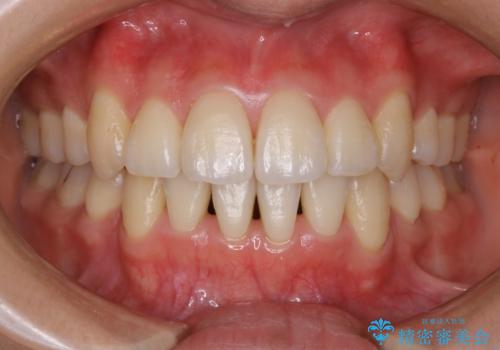

奥歯の上下のズレ等は軽度で、必要なスペースと抜歯により作られるスペースがほぼ等量だったため治療の単純化が計れ、大きな移動・見た目の劇的な変化に対して比較的早期での治療完了となりました。

叢生の度合いが重く、抜歯が必要なケース。八重歯の部分以外には大きな問題は認められなかったため、劇的変化が起こる治療でも比較的短期間で終了することができました。